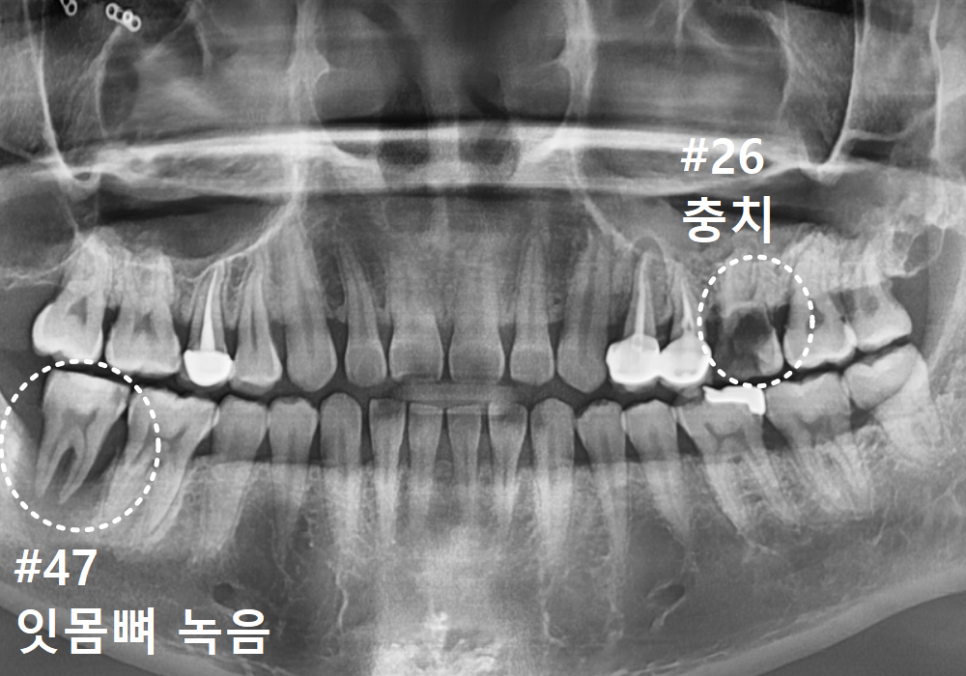

환자분께서는 왼쪽 위 어금니(#26)에 난

구멍이 점점 커지는 걸 느끼면서도,

극심한 치과 공포증 때문에 수년간

내원을 미루셨다고 해요.

그동안 불편함을 참고 주로

오른쪽으로만 식사를 하셨는데,,

이제는 믿었던 오른쪽 아래 어금니(#47)까지

흔들리기 시작하자 더는 버틸 수 없어

저희 치과를 찾아주셨어요.

입안을 보니 이미 치아가 충치로 인해

많이 삭아 있었습니다.

방사선 사진상으로는 상태가 더 심각했는데요.

보이는 것보다 충치가 훨씬 깊게 파고들어,

마치 겉면만 간신히 남고

속은 텅~비어버린 상태였어요.

더 주의 깊게 보아야 할 곳은

겉보기에 큰 충치가 없어 보였던

오른쪽 아래 치아였습니다.

방사선 사진을 보니 치아 주위의 뼈가

상당 부분 소실되어,

치아가 잇몸뼈 위에 불안정하게

떠 있는 상태였거든요.